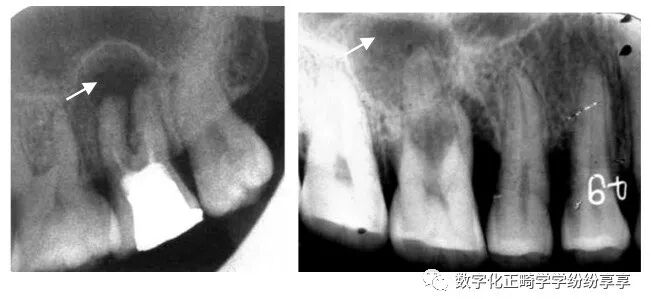

根尖周疾病 periapical disease:

根尖周脓肿

随病情发展可见病原牙为中心、骨质破坏较重、弥散性破坏、边界不清的投射区。骨硬板消失,病变一般较局限,外周可有骨质增生反应。越靠近患牙破坏越严重,密度越低

根尖周肉芽肿

在病原牙根尖根侧方或根分叉有圆形或卵圆形的密度减低区,病变范围较小,直径一般不超过 1cm,周界清楚,无质密骨硬板,病变周围骨质正常或稍变致密。

根尖周囊肿

以病原牙尖为中心形成大小不等的圆形或卵圆形、骨质破坏低密度病变区,密度均匀。边缘清晰锐利,周围骨质长期受刺激而在囊肿边缘有致密线条影。可致骨膨隆。